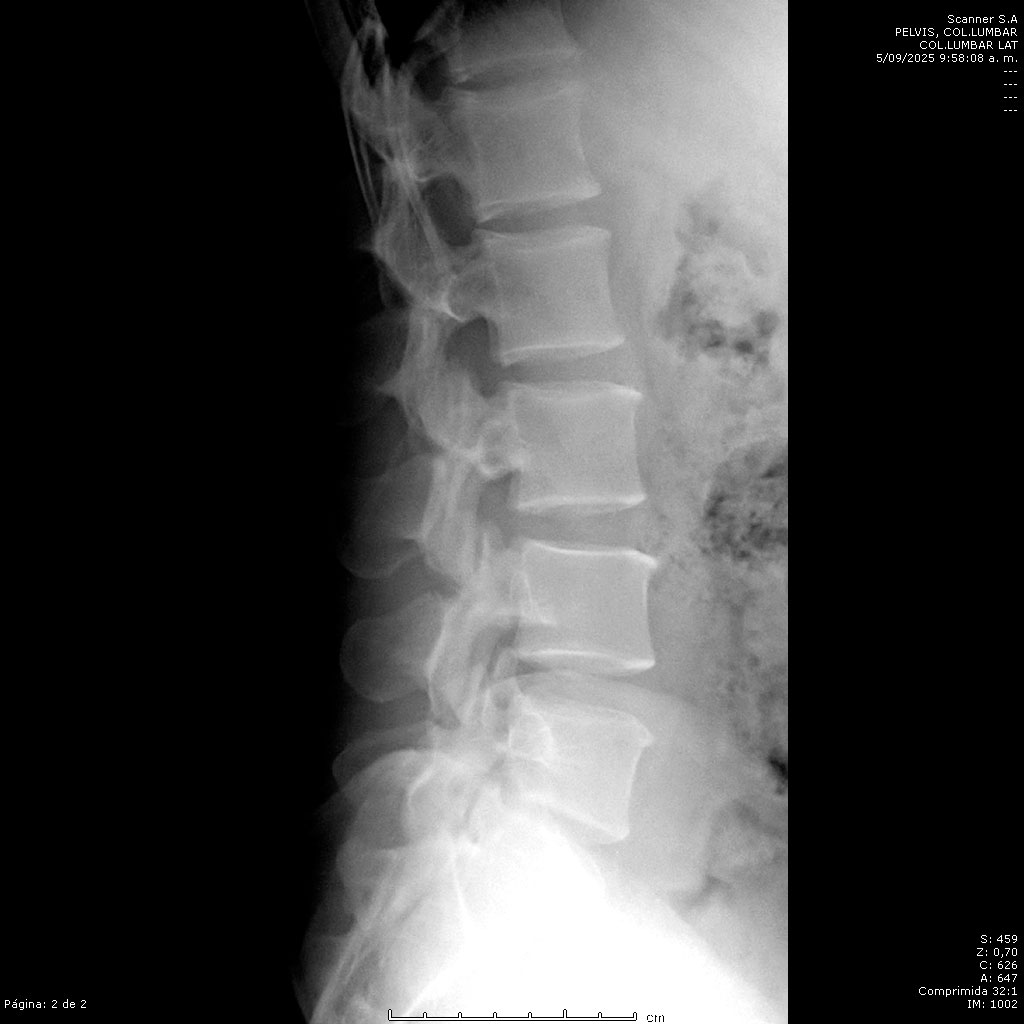

• Columna Lumbar